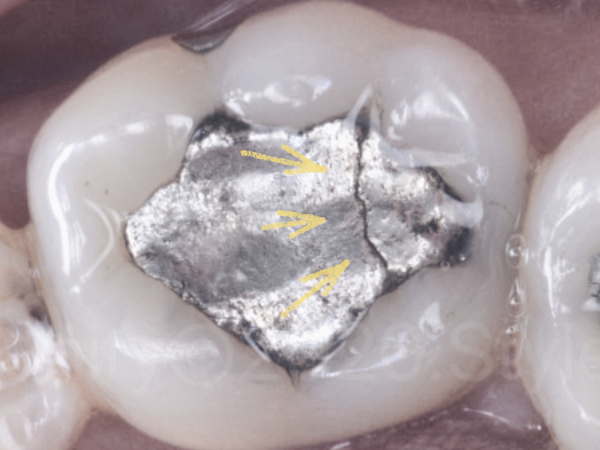

- 충전물이 깨지거나 금이 간 경우

마곡치과_충전물 균열

딱딱한 음식 씹다가

“딱” 하는 느낌… 경험 있으시죠?

그 이후로 뭔가 걸리는 느낌이 들거나

씹을 때 불편하다면

충전물이 일부 깨졌을 가능성이 있습니다.

핸드폰 액정에 금이 가면 처음엔 그냥 쓰죠.

그런데 어느 날… 쫙 퍼져 있습니다.

치아도 비슷합니다.

작은 깨짐이 더 큰 균열로 이어질 수 있습니다.